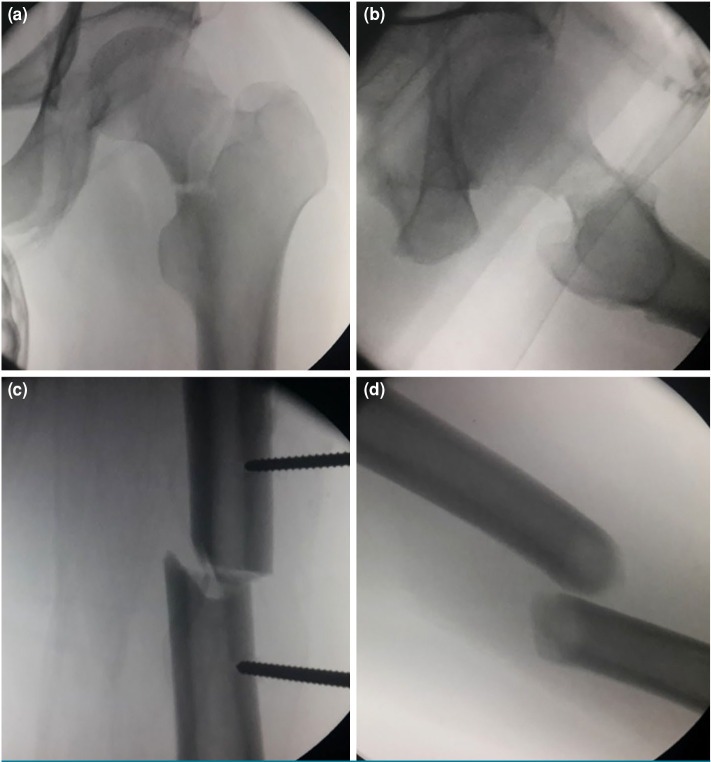

Patients and methods: Between January 2013 and December 2021, a total of 25 adult patients (19 males, 6 females, mean age: 32.8±10.9 years; range, 19 to 57 years) who sustained concurrent ipsilateral femoral neck and shaft fractures were included. The patients underwent internal fixation using a reconstruction nail with the assistance of a reductor-T tape pin, employing percutaneous techniques. The operation time, reduction time, fluoroscopy time, blood loss, preoperative and postoperative Visual Analog Scale (VAS) scores, fracture union time, Harris scores of the healthy and affected sides after fracture union, complications and lower limb functional outcomes two years post-surgery were recorded.

Results: All patients underwent successful surgery with the assistance of the reductor-T tape pin using percutaneous techniques without the need for open reduction. The mean operation time from skin incision to wound closure was 80.0±15.0 (range, 55 to 105) min. The mean fracture reduction time was 22.0±4.0 (range, 15 to 28) min. The mean fluoroscopy time was 16.0±3.8 (range, 9 to 25) sec. The mean blood loss was 335.0±142.0 (range, 150 to 550) mL. The postoperative VAS score of the affected limb was significantly lower than the preoperative score (p<0.01). The mean healing time of femoral neck fractures was 4.0±0.3 (range: 3.2 to 4.8) months. The mean healing time of femoral shaft fractures was 4.8±0.9 (range, 4.1 to 7.5) months. All patients were followed for over two years. No cases of delayed healing of femoral neck fractures or femoral head necrosis were observed. However, delayed union of femoral shaft fractures occurred in three patients. There was no statistically significant difference in Harris scores between the affected and healthy sides at the time of fracture healing (p>0.05).

Conclusion: The use of a reconstruction nail assisted by the percutaneous reductor-T tape pin demonstrated successful reduction of ipsilateral femoral neck and shaft fractures, with favorable postoperative functional outcomes. The reductor-T tape pin facilitates the reduction of femoral neck fractures and provides a safe environment for the reduction and fixation of femoral shaft fractures.